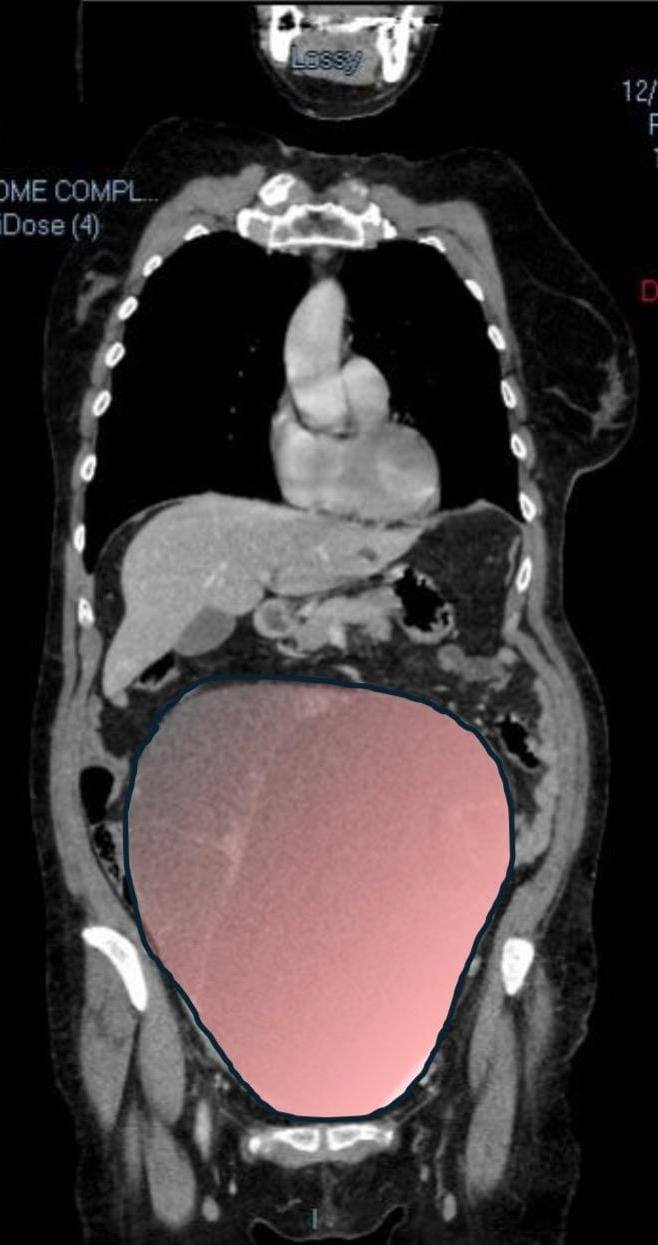

Timp de luni de zile, chistul ovarian gigant, cu un diametru de aproximativ 28 de centimetri, a rămas ascuns, fără a da semne evidente. Pacienta nu observase nimic.

Alarma a fost dată când masa, asociată cu prezența unui al doilea neoplasm intestinal, a început să comprime colonul, provocând dificultăți intestinale severe.

În timpul operației, gravitatea situației a devenit evidentă. Tumora ovariană gigantică a fost îndepărtată: cântărea aproximativ 6 kilograme, având un volum comparabil cu cel al unei sarcini gemelare la termen. Cele mai periculoase simptome erau legate de tulburările intestinale, care necesitau intervenția imediată și coordonată a mai multor specialiști.